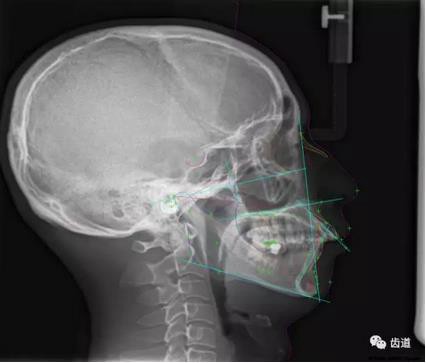

五)口腔正畸

CBCT在頜骨正畸科方面的應(yīng)用:軟件功能的強(qiáng)大,提供有效的數(shù)據(jù),為頜骨正畸提供了極大的幫助,免除了很多臨床醫(yī)生的手工繪圖,并有利于科研、教學(xué)等方面發(fā)展研究。

投影測(cè)量側(cè)位片影像

軟件產(chǎn)生CEPH圖像注釋?zhuān)缓琗線射線圖像